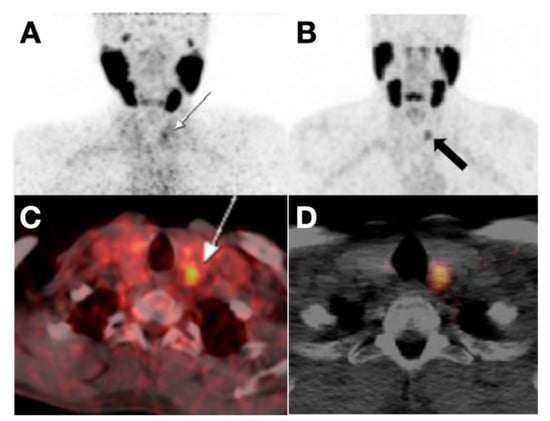

- Parihar, A.S.; Mittal, B.R.; Kumar, R.; Shukla, J.; Bhattacharya, A. 68Ga-DOTA-RGD2 Positron Emission Tomography/Computed Tomography in Radioiodine Refractory Thyroid Cancer: Prospective Comparison of Diagnostic Accuracy with 18F-FDG Positron Emission Tomography/Computed Tomography and Evaluation Toward Potential Theranostics. Thyroid Off. J. Am. Thyroid Assoc. 2020, 30, 557–567. [Google Scholar] [CrossRef]

- Parihar, A.S.; Sood, A.; Kumar, R.; Bhusari, P.; Shukla, J.; Mittal, B.R. Novel Use of 177Lu-DOTA-RGD2 in Treatment of 68Ga-DOTA-RGD2-Avid Lesions in Papillary Thyroid Cancer with TENIS. Eur. J. Nucl. Med. Mol. Imaging 2018, 45, 1836–1837. [Google Scholar] [CrossRef]